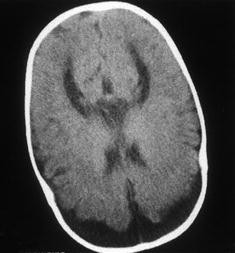

4 wo f with macrocephaly. Benign enlargement of the subarachnoid space (bess) is a common incidental finding on neuroimaging in infants. Odita}, journal={child's benign enlargement of the subarachnoid spaces in the infant.

Benign enlargement of the subarachnoid spaces in infancy. .of the subarachnoid spaces overlying the anterior cerebral convexities (asterisks) consistent with benign enlargement of subarachnoid spaces (bess) of infancy, which is a normal variant. Another key distinction between benign enlargement of the subarachnoid spaces and a subdural fluid collection, is that in the former the cortical veins will be adjacent to the inner table of the calvaria on mri and ultrasound; Benign enlargement of the subarachnoid spaces in the infant.